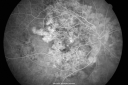

84-year-old woman has polypoidal choroidal vasculopathy in both eyes with macular degeneration. She has macular scars in both eyes and she remains with remarkably good vision in the right eye despite the scarring.

VISUAL ACUITY: OD 20/30, OS 1/200. IOP: OD 13, OS 16. The posterior chamber intraocular lens is in good position in both eyes.

OD: Vertical C/D ratio is 0.2. There is subretinal fibrosis superior, inferior, nasal and temporal to the fovea. The fovea though is relatively spared.

OS: Vertical C/D ratio is 0.2. There is an elevated disciform scar about 8 disc-diameters across, which extends outside the arcades all the way around. Photos confirm clinical findings.

FLUORESCEIN ANGIOGRAPHY: Fluorescein angiography shows irregular hyperfluorescence and staining of subretinal fibrosis, which extends through the fovea. The left eye also has staining subretinal fibrosis. Neither eye has any evidence of any leakage.